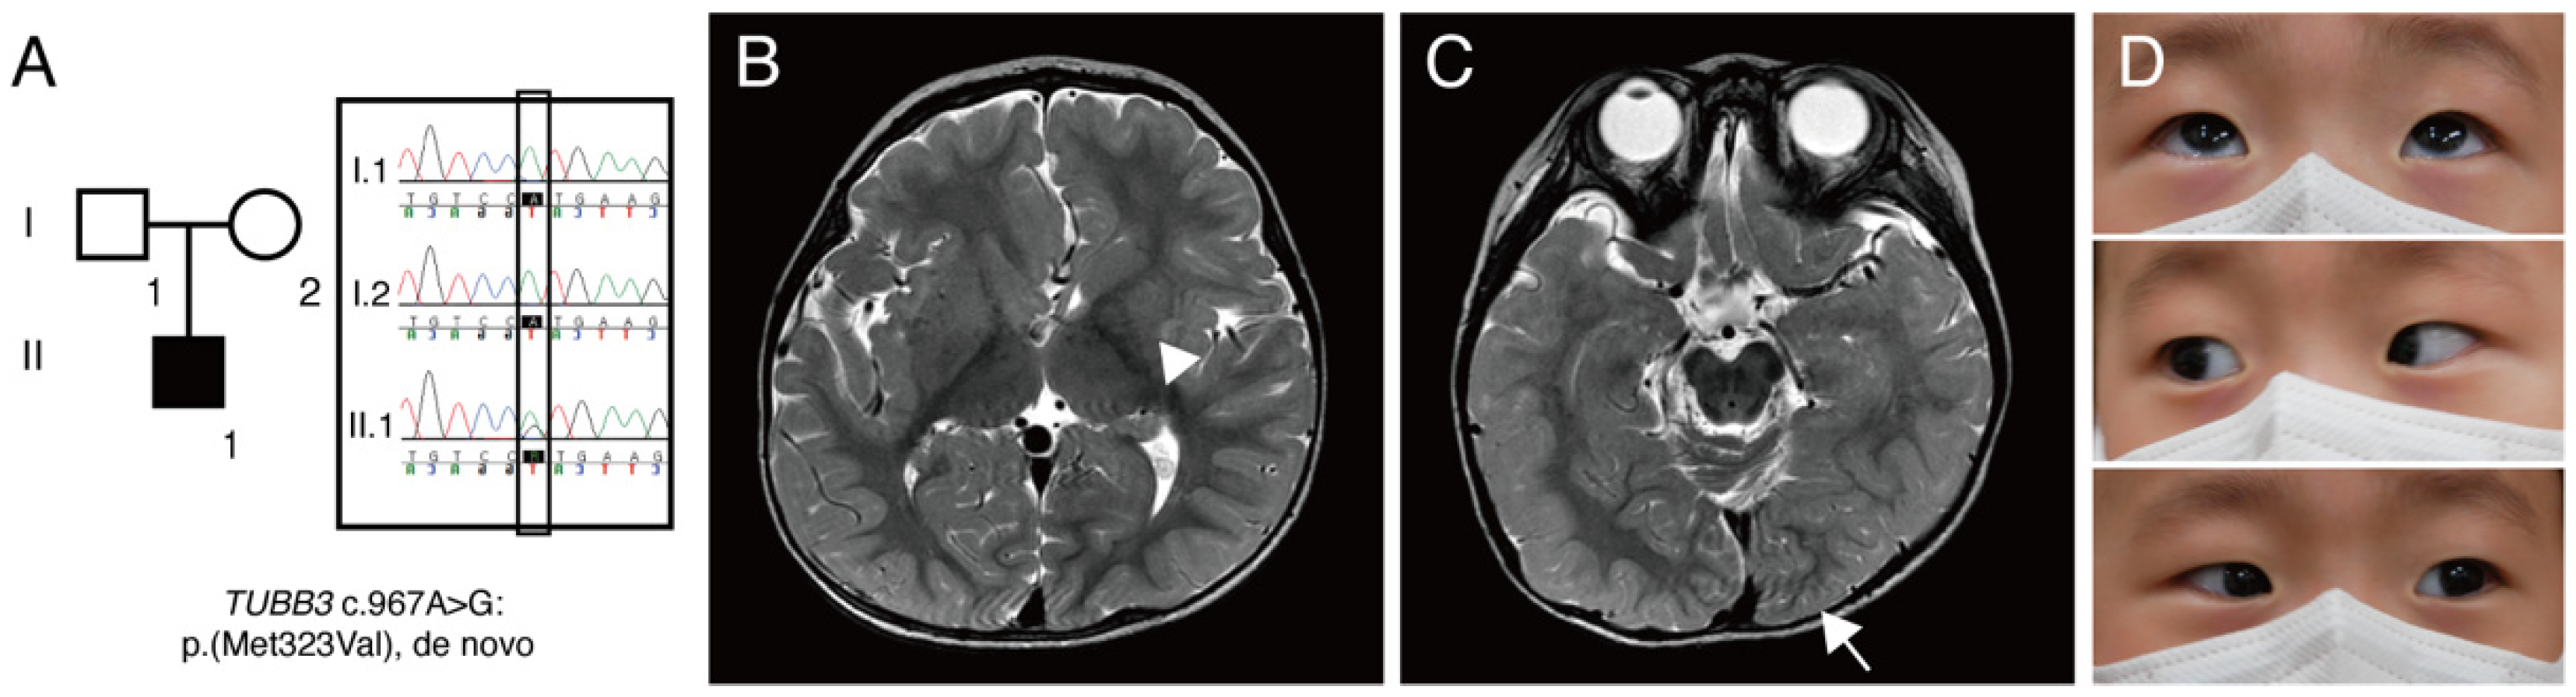

| TUBB3 variant | p.M323V | p.M323V | p.A302V (homo) | p.G71R | p.G71R | p.G98S | p.M323V | |

| Inheritance pattern | AD | AD | Isolated (homo) | Isolated | Isolated | Isolated | Isolated | |

| Age | 36 years | 2 years | 1 year | 5 years | 9 years | 2 years | 6 months | |

| Gender | Male | Male | Female | Female | Male | Female | Male | |

| Ethnicity | NA | NA | NA | European | European | European | Korean | |